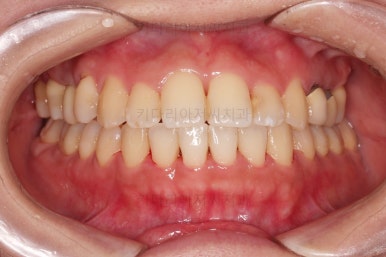

임플란트 보철이 깔끔하게 들어갔고, 교정치료도 마무리가 되었습니다.

부산연산동치과 전후 사진을 비교해 보겠습니다.

총 22개월 걸렸고, 임플란트는 1개로 마무리를 했습니다.

처음에 충분히 다양한 치료옵션을 제시해 드렸었고, 입을 넣느냐/마느냐 임플란트를 안하느냐/1개를 하느냐, 기간이 많이 걸리느냐/적게 걸리느냐 등 다양한 관점에서 가장 합리적이다라고 판단되는 옵션을 선택하시어 그에 부합하는 치료로 마무리가 되었습니다.

이상 부산연산동치과 치아 상실의 경우 치아교정과 임플란트를 병행 치료했던 사례였습니다.